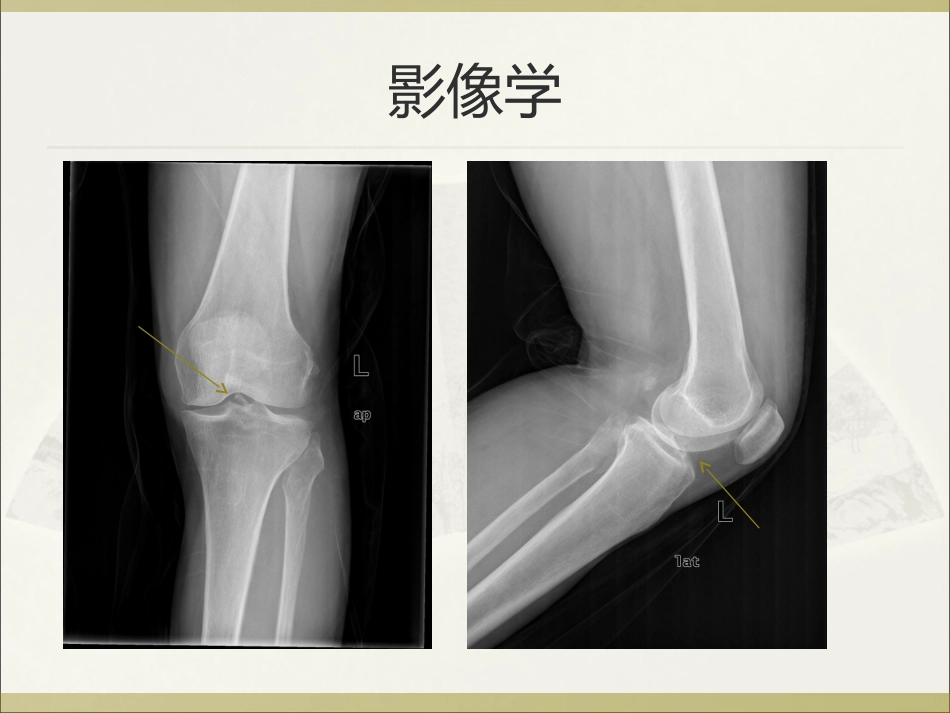

关节镜下应用缝合锚钉固定治疗前交叉韧带胫骨止点撕脱性骨折关节外科临床资料2007年1月至2009年12月12例患者,其中男8例,女4例按Meyers-McKeever分型:Ⅱ型8例,Ⅲ型17例,Ⅳ型5例12例患者均获得随访,时间10个月~3年,平均20个月影像学MRMR治疗方法保守治疗I型及部分II型关节稳定,并且无关节伸直受限膝关节支具15度固定,3周后开始调整角度及功能锻炼手术治疗II至IV型骨折手术治疗镜检情况具体步骤术后复查结果所有患者骨折均愈合,术后恢复良好,无膝关节不稳及膝关节僵硬症状10例新鲜骨折病例获得6个月以上随访,术后Lysholm评分平均96.4分2例陈旧骨折病例,术后Lysholm评分平均89.8分讨论损伤特点多见于儿童和青少年ACL的胶原纤维在儿童和青少年是与胫骨棘软骨膜相连的,当ACL受到暴力时,其韧带下端可发生大块撕脱骨折多因急速减速,膝关节猛烈屈曲所致高彦平等,前交叉韧带胫骨棘止点撕脱骨折损伤机制及诊治,南方医科大学学报(JSouthMedUniv),2008;28(11)诊断能见度是指是否所有的断裂边缘可以看到,即可以得到充分的断裂划定CT有较大优势分型Meyers-McKeever分型:I型:撕脱的骨块轻度移位,即在前缘有轻度翘起II型:撕脱骨块移位较大,前1/3~1/2部自平台翘起分离,侧位像可见一鸟嘴样折块III型:撕脱骨块完全自平台分离,骨块发生移位但有与正常相似的排列IV型:骨块粉碎并有旋转成角(国内)MeyersMH,McKeeverFM.Fractureoftheintercondylareminenceofthetibia.JBoneJointSurgAm1970;52:1677-1684.内固定选择螺丝钉内固定MehmetSB认为,螺丝钉内固定是处理该类型骨折的最理想方法前提是骨折块不能粉碎,且其体积至少是螺钉帽的3倍大小内固定选择缝线及钢丝内固定需要打胫骨隧道胫骨结节前内侧需单独切口钢丝需二次手术取出,部分患者不接受吴宇峰等报道,缝线内固定优于钢丝内固定效果吴宇峰等,前交叉韧带胫骨棘止点撕脱骨折不同内固定方式的生物力学研究,中华创伤骨科杂志,2008,8(9):868-871缝合锚钉固定的优点全镜下操作,不需要附加切口无损伤骨骺的风险不需要取出内固定物固定牢稳可靠结论应用缝合锚钉固定前交叉韧带胫骨止点撕脱骨折创伤小,术后功能恢复良好无骨骺损伤风险,特别适用于儿童及青少年患者谢谢